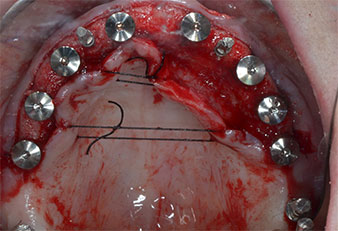

Debido al hueso relativamente duro (D2) existente en el sector anterior, los sitios de los implantes largos de 10 mm de las posiciones 11 y 21 se finalizaron con una fresa rotatoria de 4 mm de diámetro, en combinación con un contra-ángulo quirúrgico WS-75 L de W&H, el motor de implantes Implantmed de W&H y el módulo opcional Osstell ISQ de W&H. En cambio, debido a la existencia de hueso blando, los sitios posteriores se prepararon hasta un diámetro final de 3 mm utilizando el inserto Piezomed I3P. Por último, los implantes se colocaron a nivel crestal para su osteointegración durante tres meses (figuras 6-10). La prótesis existente se mantuvo sobre cuatro implantes provisionales (figura 8).

Implante en el nivel de tejido de 10 mm

Fig. 6: En la posición 21 se colocó un implante en el nivel de tejido de 10 mm. El implante de la posición 11 y los tres implantes posteriores izquierdos de 4 mm ya estaban colocados en su lugar.

Implantes provisionales

Fig. 8: Después de la fijación de los formadores de encía, se colocaron implantes provisionales en las posiciones 18, 12, 22 y 28.

Plantilla de plástico

Fig. 9: Una plantilla de plástico mostró que había suficiente espacio para que la prótesis existente sirviera como prótesis temporal sujeta en los implantes provisionales.